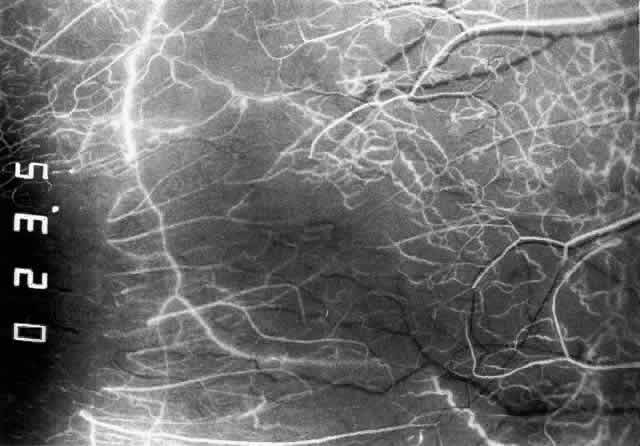

ARTERIAL PHASE Anterior Episcleral Arterial Circle The anterior ciliary arteries run radially toward the limbus within Tenon's capsule, giving few, if any, branches until they reach the anterior part of the globe. Their positions are very variable, and they do not always follow the rectus muscles. They bifurcate 2 to 5 mm behind the limbus, and each division runs forward and circumferentially to anastomose with a branch from an adjacent artery. This results in an anterior episcleral arterial circle (Figs. 3 through 5). The divisions of the anterior ciliary arteries are typically superficial at their origins but run deeper at their anastomoses. They occasionally dip too deep to be seen in fluorescein angiograms (Fig. 6).

From the anterior episcleral arterial circle, four distinct circulations are supplied: episcleral, anterior conjunctival, limbal, and iris. Episcleral Circulation Immediately after their origin by bifurcation of the anterior ciliary arteries, the contributions to the anterior episcleral circle divide again to give recurrent branches that run posteriorly and subdivide to form a netlike episcleral plexus (see Fig. 5; Fig.7). The variability of the positioning of the anterior ciliary arteries inevitably leaves large areas of episclera far from such an arterial supply (see Figs. 4, 6, and 7). These areas receive other posterior branches from the episcleral circle. Where the circle runs deep within the sclera, such branches appear as isolated perforating vessels (see Fig. 6). They fill very shortly after the episcleral circle, and they also divide repeatedly as they run posteriorly.

Anterior Conjunctival Circulation Throughout their superficial course, the arteries of the episcleral circle give off fine loops that run forward into the limbal reflection of the conjunctiva before curving back radially and dividing to form the lacework of the anterior conjunctival capillary plexus (see Fig. 2). The delicate column of blood within the anterior conjunctival loops may be punctuated by a string of individual erythrocytes, suggesting that the lumen is approximately 12 μm in diameter. Anterior conjunctival loops may also arise from perforating posterior branches of the episcleral circle (see Fig. 6). The anterior conjunctival circulation, supplied by the anterior ciliary arteries, always fills before the posterior conjunctival circulation, which is derived from the posterior tarsal vessels (see Figs. 4 and 5). The watershed zone between these sources can fill very late (see Fig. 5). However, anterior conjunctival loops do sometimes anastomose with arteries of similar caliber derived from the posterior tarsal circulation. Limbal Arcades Limbal arcades are supplied by anterior branches from the episcleral circle. Their origins are often shared with those of the anterior conjunctival loops, and, where the circle runs deep, they too are derived from the perforating posterior branches. They often fill very late during a normal angiogram (see Fig. 7). The limbal capillary loops never leak fluorescein, even during high-dose angiograms, suggesting that their endothelial cells are united by tight junctions. Iris Vessels The first flush of fluorescein within the anterior episcleral arterial circle always coincides with filling of the radial arterioles of the iris. It may be implied from this that the iris receives a major supply from the anterior ciliary circulation (see Fig. 6). In some angiograms, the iris circulation appears to derive directly from the episcleral circle. This raises the possibility that the “major circle of the iris” and the episcleral arterial circle are less distinct entities than has hitherto been presumed. VENOUS PHASE Anterior ciliary veins accompany the arteries, but there is no well-organized venous ring corresponding to the anterior episcleral arterial circle. The posterior episcleral branches of the arterial circle are paralleled by centripetal venules, and looping anterior conjunctival venules are interspersed between the arterioles (see Figs. 4 and 5). The posterior conjunctiva drains back into the tarsal circulation. CAPILLARY PHASE The episcleral capillary net is often difficult to discern below the more prominent conjunctival circulation. It is most clearly seen when the conjunctival circulation fills late for anatomic or pathologic reasons. The anterior conjunctival capillary plexus forms an interlacing network between the anterior conjunctival arterioles. Perfusion of the watershed zone that separates the territories supplied by the anterior ciliary and posterior tarsal systems may be delayed by as much as 15 seconds after first flush (see Figs. 5 and 7). However, this region is often crossed by arteriolar anastomoses between the two circulations, and the destination of venous blood is irrespective of its origin from the anterior ciliary or posterior tarsal circulations. |